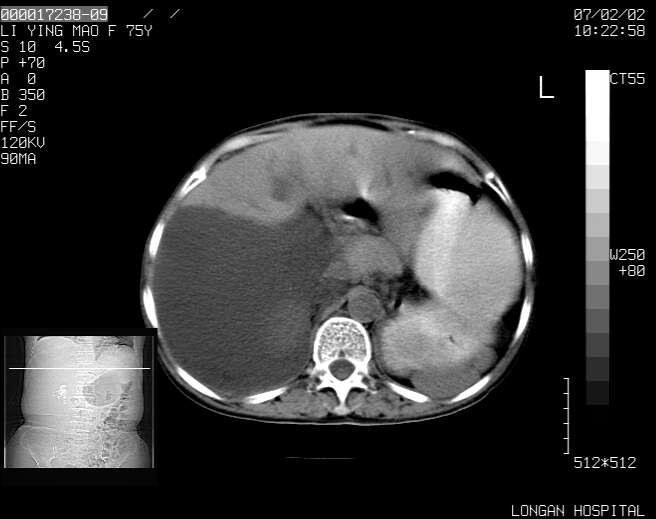

以下是引用dyqct在2007-2-10 8:53:00的发言:[br]考虑:1、肝脏多发囊肿[br] 2、左肾囊肿,右肾多发结石并积水。[br] 3、右胸少量积液。[br] 4、右肾周包裹性积液或淋巴管瘤(有见缝就钻的征象、薄隔、小结节状钙化)?[br] 5、腰椎动脉瘤样骨囊肿?[br] [br] [br]